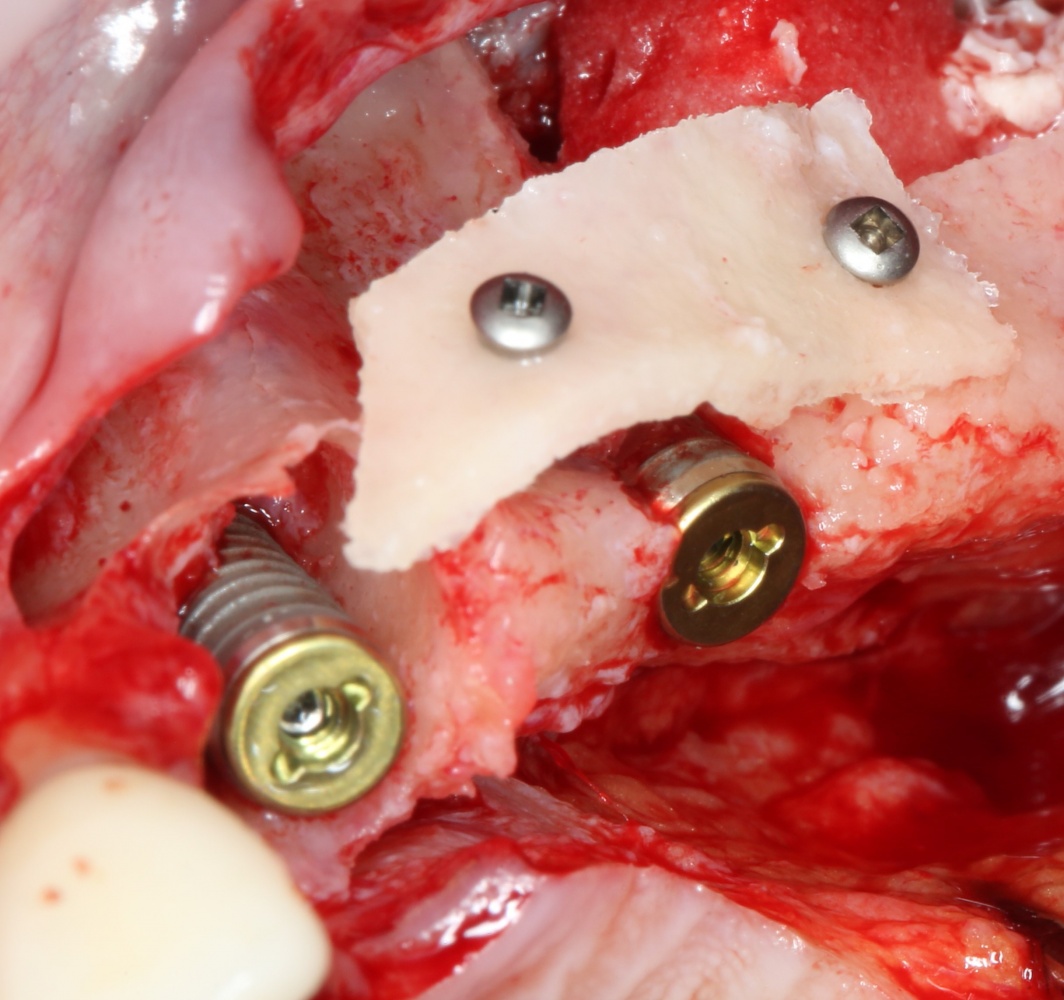

Итак, мы удаляем клык, по шаблону устанавливаем импланты, строим «каркас» будущего альвеолярного гребня в области пятерки:

Для синуслифтинга мы используем Geistlich Bio-Oss, который пригодился нам как для остеопластики (наполнения построенного «каркаса»), так и для аугментации лунки:

Проводя остеопластику, мы не забываем о «факторах успеха остеопластических операций«, в частности о факторе #3. Поэтому, несмотря на то, что «классикой» немедленной имплантации является установка формирователя десны, мы перекрываем лунку клыка барьерной мембраной и ушиваем ее наглухо: